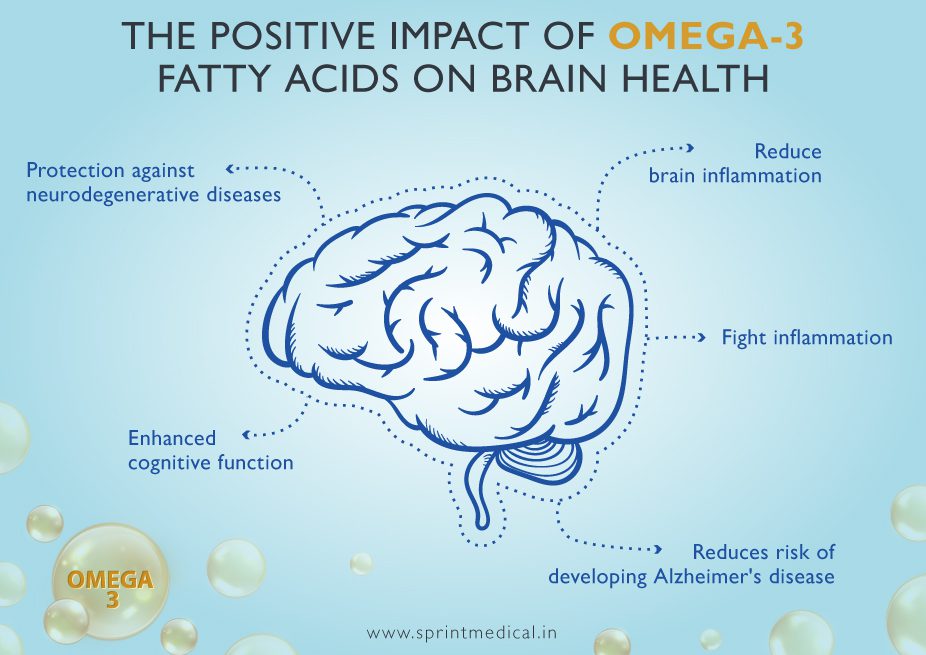

2️⃣ Enhances Brain Function

DHA is a structural component of the brain. Adequate intake may support:

Memory

Focus

Cognitive performance

Some research also explores its role in mood balance and mental clarity.

3️⃣ Reduces Inflammation

Chronic inflammation is linked to various health conditions. EPA plays a role in regulating inflammatory responses.